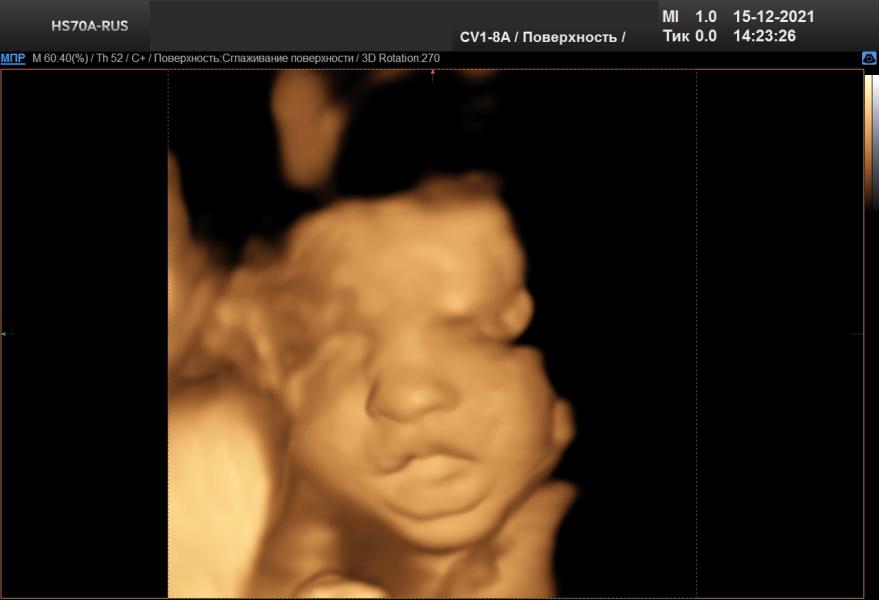

Третий скрининг) 3D) показывала нам язык, хлопала глазками и тянула кулачки в рот))

Наоборот, врач сказала, что на более поздних сроках, чем у меня, дети фиксируются и так сильно не шевелятся как было в моем случае и видно четче